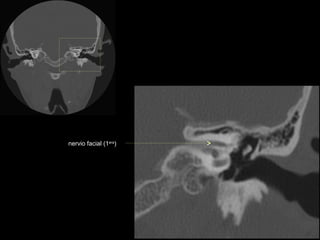

nervio facial

nervio facial (2da)

nervio facial (1era)